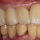

SMART BEFORE & AFTER

눈에 보이는 변화,

느끼는 자신감!

실제 치료 전과 후를 확인하세요.